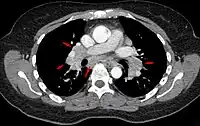

La enfermedad puede manifestarse en cualquier órgano del cuerpo, con mayor frecuencia en el pulmón y ganglios intratorácicos. También son frecuentes las manifestaciones oculares, cutáneas y hepáticas.

Su diagnóstico generalmente se hace por exclusión con una clínica compatible, imágenes radiológicas sugerentes y la confirmación histológica con presencia de granulomas no caseosos.